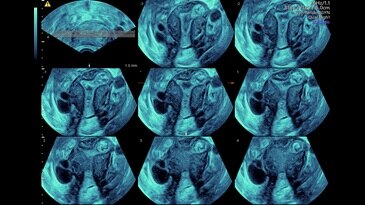

TUI (Tomography Ultrasound Imaging): Siêu âm cắt lớp

Tomographic ultrasound imaging (TUI) of uterine cavity